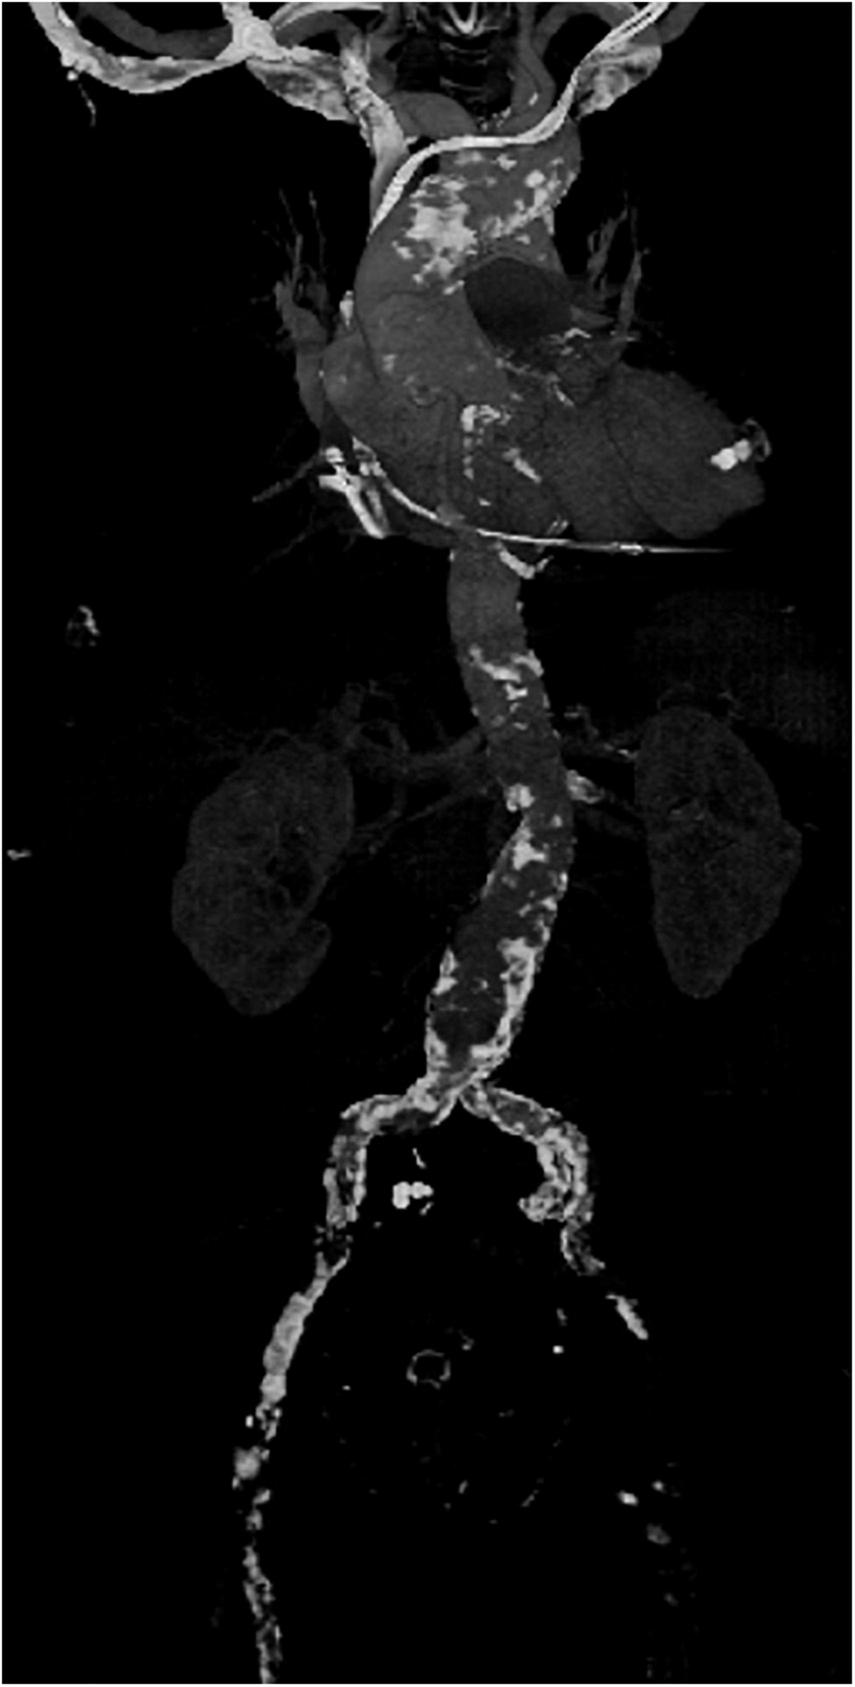

FIGURE 2

Example of a computed tomography (CT) scan of the aorta of a patient with severe arteriosclerosis in the axillary artery, aortic arch abdominal aorta and especially the femoral vessels in which minimally-invasive surgery was performed by using an antegrade arterial perfusion via arteria axillaris.